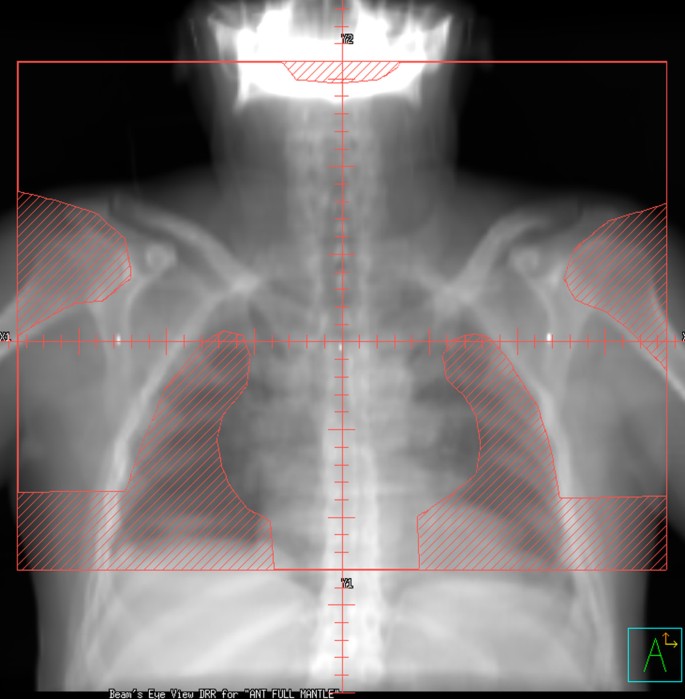

Patients were planned in the supine position, with neck extended, typically with arms akimbo and the upper torso immobilized in a Bodyfix® device. For each patient, three treatment plans were constructed using the patient's planning CT data set: 35 Gy in 20 fractions mantle RT (historic treatment), 35 Gy in 20 daily fractions IFRT (current treatment), and 20 Gy in 10 daily fractions IFRT (potential future practice). Figures 1 and 2 show digitally reconstructed radiographs demonstrating typical RT field borders for 35 Gy mantle RT and IFRT, respectively.

Mantle fields were designed according to accepted anatomic landmarks [20], extending from the mastoid process superiorly to the diaphragmatic insertion inferiorly, encompassing the bilateral axillae and extending laterally just beyond the humeral heads. Lung shields were placed 10–15 mm from the mediastinal contour and laterally followed the inner rib margins. Humeral head shielding throughout the RT course, as well as anterior laryngeal and posterior spinal cord shielding introduced at 24.5 Gy was planned. The cardiac dose was limited to = 30 Gy, below a transition zone located at 50 mm inferior to the carina.